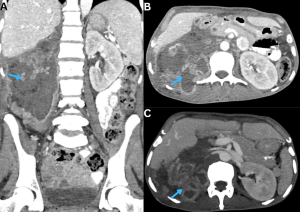

Fig 22: Clinical history:

A known case of disseminated mucormycosis presented with abdominal pain, fever, and acute kidney injury.

Figure A:

Axial HRCT chest image demonstrates both the halo sign (blue arrow) and reverse halo sign (red arrow), consistent with invasive pulmonary fungal infection.

Figures B & C:

Axial and coronal contrast-enhanced CT (CECT) abdomen images demonstrate nonenhancement of the left kidney (green arrow) with severe paucity of contrast opacification in the left renal artery (white arrow). Multiple wedge-shaped nonenhancing areas are noted in the right kidney (yellow arrows), consistent with bilateral renal infarctions. An additional wedge-shaped nonenhancing area is seen in the inferior pole of the spleen (orange arrow), consistent with splenic infarction.